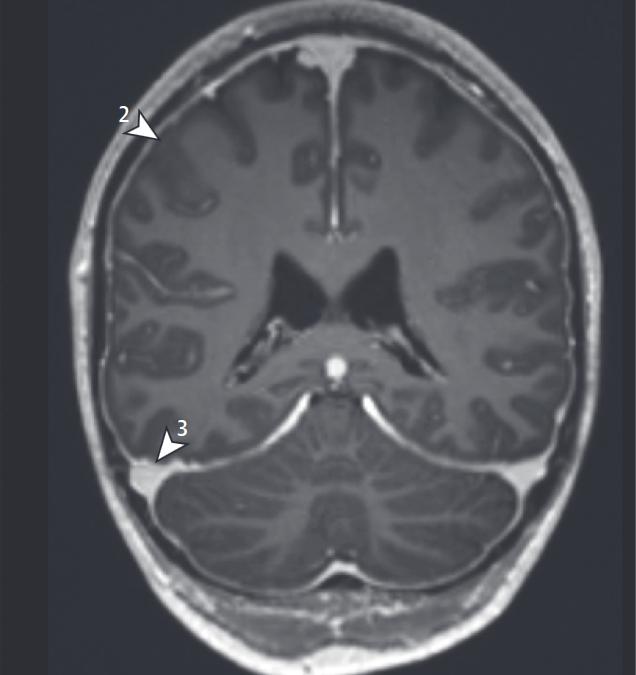

SIH Score

2) Pachymeningeale Enhancement 3) Vergrößerung der Sinus durae matris. Dobrocky T. et al. 2019. JAMA Neurology.